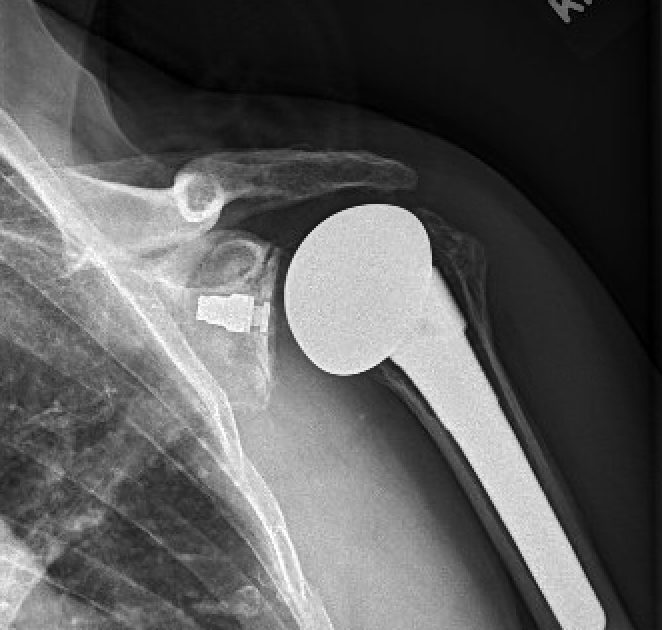

2. What are the specific failure modes driving revisions, and are those modes changing over time? For anatomic TSA, are the rates of glenoid component loosening, instability, rotator cuff failure, and infection getting higher, lower or staying the same? For reverse TSA how are the rates of instability and dislocation, acromial and scapular spine fracture, infection, notching with component loosening, and periprosthetic fracture changing with time?

The total shoulder arthroplasty (see this link).

The reverse total shoulder arthroplasty (see this link).